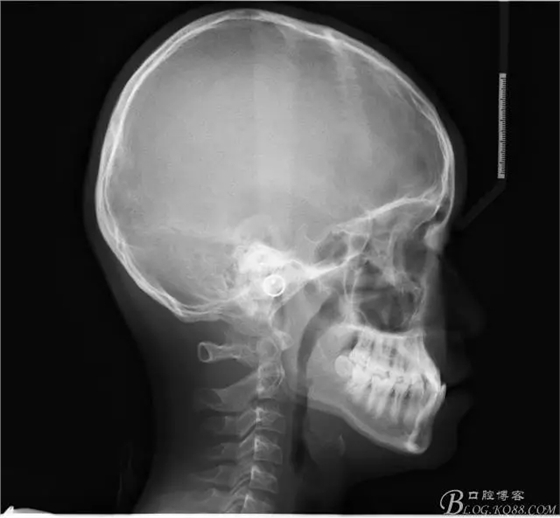

患者13歲,男性,自覺牙齒不齊要求矯正;

640.webp.jpg

640.webp (1).jpg